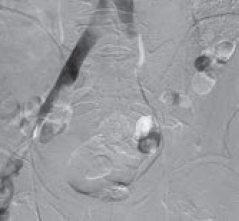

Рис. 3. Антеградная илеокаваграфия у пациента М., 39 лет, с выраженной тазовой симптоматикой (боли, эректильная дисфункция, хронический калькулезный простатит) вследствие синдрома Мея – Тюрнера: а — антеградная катетеризация левой общей подвздошной вены; б — при введении рентгеноконтрастного вещества отмечается его ретроградный заброс и контрастирование венозных сплетений малого таза (коллатеральное кровообращение); в — после контрастирования венозных сплетений малого таза рентгеноконтрастное вещество перераспределяется в правую общую подвздошную вену. Диаметр правой общей подвздошной вены в 1,4 раза меньше диаметра левой общей подвздошной вены